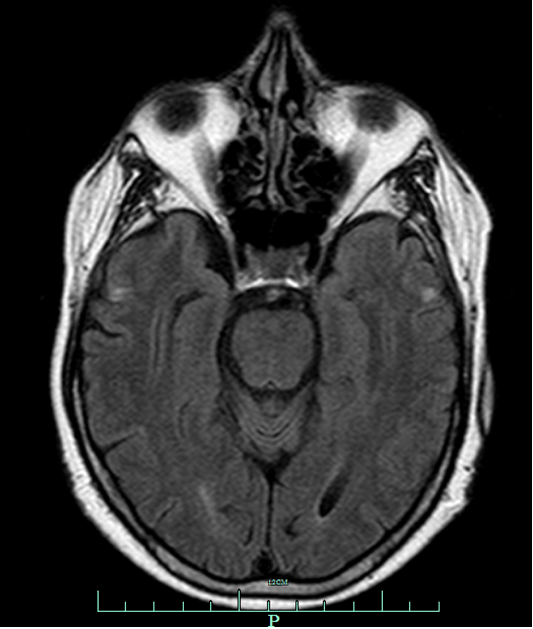

During the second day of hospitalization, the patient complained of neck pain. MRI of cervical spine showed abnormal signal in the pons. Brain MRI, T2-weighted and Fluid Attenuated Inversion Recovery (FLAIR) both revealed a hyperintense lesion in the pons. Diffusion weighted image showed hyper-intensity within the central pons with restricted diffusion on ADC (Figure 2A-D). Findings were consistent with CPM. The sodium level was 130 mmol/L essentially excluding rapid correction of hyponatremia as a cause for CPM.

Figure 2: Brain MRI: Axial diffusion weighted image (A) showing hyper-intensity within the central pons with low signal on ADC (B) in keeping with restricted diffusion. Axial T2 weighted (C) and FLAIR (D) sequences demonstrate increased signal with the central pons.